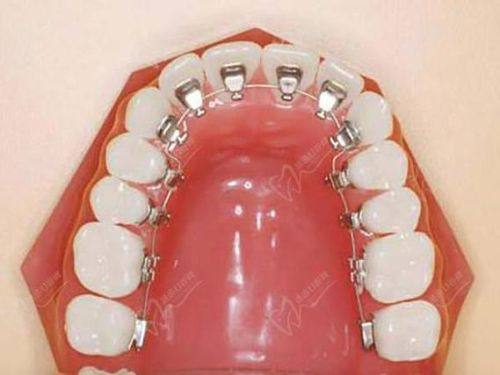

15. 舌侧矫正:30000 - 60000元